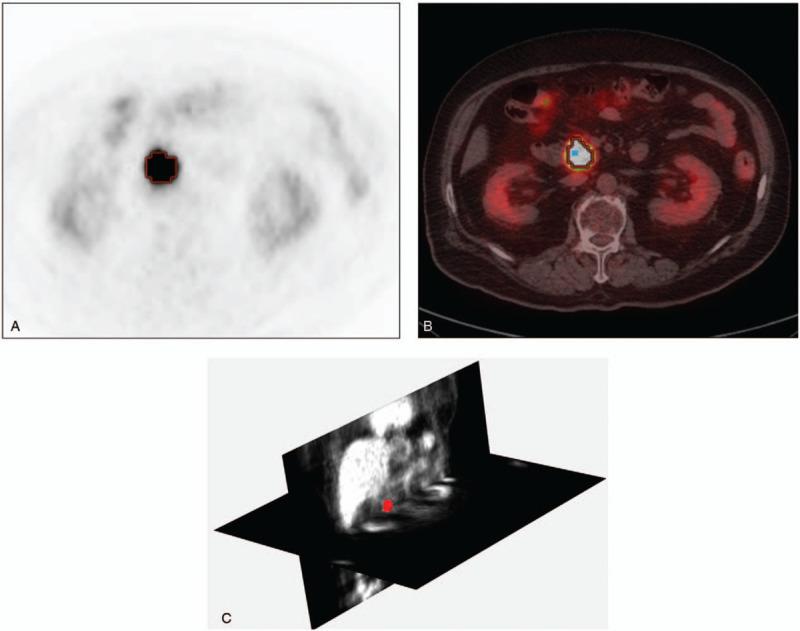

Imaging parameters including metabolic or textural parameters during F-18 fluorodeoxyglucose (FDG) positron emission tomography/computed tomography (PET/CT) are being used for evaluation of malignancy. However, their utility for prognosis prediction has not been thoroughly investigated. Here, we evaluated the prognosis prediction ability of imaging parameters from preoperative FDGPET/CT in operable pancreatic cancer patients.Sixty pancreatic cancer patients (male:female = 36:24, age = 67.2 ± 10.5 years) who had undergone FDGPET/CT before the curative intent surgery were enrolled. Clinico-pathologic parameters, metabolic parameters from FDGPET/CT; maximal standard uptake value (SUVmax), glucose-incorporated SUVmax (GI-SUVmax), metabolic tumor volume, total-lesion glycolysis, and 53 textural parameters derived from imaging analysis software (MaZda version 4.6) were compared with overall survival.All the patients underwent curative resection. Mean and standard deviation of overall follow-up duration was 16.12 ± 9.81months. Among them, 39 patients had died at 13.46 ± 8.82 months after operation, whereas 21 patients survived with the follow-up duration of 18.56 ± 9.97 months. In the univariate analysis, Tumor diameter ≥4 cm (P = .003), Preoperative Carbohydrate antigen 19-9 ≥37 U/mL (P = .034), number of metastatic lymph node (P = .048) and GI-SUVmax (P = .004) were significant parameters for decreased overall survival. Among the textural parameters, kurtosis3D (P = .052), and skewness3D (P = .064) were potentially significant predictors in the univariate analysis. However, in multivariate analysis only GI-SUVmax (P = .026) and combined operation (P = .001) were significant independent predictors of overall survival.The current research result indicates that metabolic parameter (GI-SUVmax) from FDGPET/CT, and combined operation could predict the overall survival of surgically resected pancreatic cancer patients. Other metabolic or textural imaging parameters were not significant predictors for overall survival of localized pancreatic cancer.

纳入了60例在进行根治性手术前接受过FDG PET/CT检查的胰腺癌患者(男:女 = 36:24,年龄 = 67.2±10.5岁)。将临床病理参数、FDG PET/CT的代谢参数;最大标准摄取值(SUVmax)、葡萄糖掺入SUVmax(GI-SUVmax)、代谢肿瘤体积、总病变糖酵解以及从成像分析软件(MaZda版本4.6)得出的53个纹理参数与总生存期进行比较。